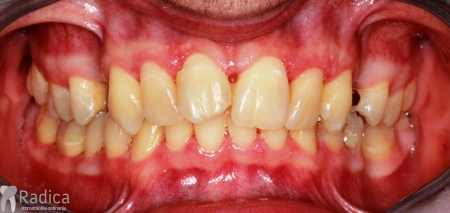

Osim toga, u donjoj čeljusti su bili izvađeni lijevi drugi premolar „petica“ i prvi molar „šestica“. Također, pacijent je imao i otvoreni zagriz te protruziju frontalnih zuba (bili su izbačeni naprijed). Nakon dijagnostike odlučeno je da se na mjesto izgubljenog sjekutića pomakne lateralni sjekutić „dvojka“, te ekstrakcija prvog gornjeg lijevog i donjeg desnog premolara „četvorke“ radi rješavanja protruzije zuba i otvorenog zagriza. Na mjesto izgubljenog prvog donjeg lijevog molara je nakon terapije stavljen implantat – rad dr. Gorana Radice.